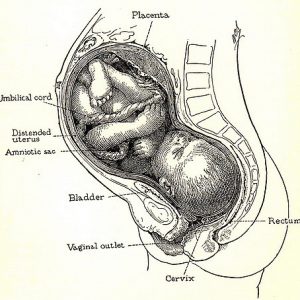

Com 30 semanas de gravidez o bebê ainda não tem controle total sobre as suas mãos, mas é capaz de segurar o cordão umbilical e puxar seus cabelos quando encontrá-los. Nesta etapa o bebê está dividindo espaço com cerca de 1 litro de líquido amniótico, que tem extrema importância para sua sobrevivência no útero. Esse líquido irá reduzir naturalmente, acompanhando o crescimento do bebê. Ele deve ser monitorado através dos ultrassons solicitados pelo obstetra.

Seus pulmões, assim como seu sistema respiratório e digestivo, já estão aptos para trabalhar2. A partir da 30ª semana de gestação, agora seu crescimento irá ficar mais lento. O foco é ganhar peso, e isso será bem rápido até o nascimento. Sua pele já é lisa e rosada devido ao acúmulo de gordura que ele já possui abaixo da pele. É possível que sinta os movimentos ficarem mais lentos, mas não se preocupe, é normal. Isso é devido ao pouco espaço que o bebê passa a ter com seu crescimento.

Às 30 semanas de gestação, um novo sintoma pode começar a bater à sua porta: a dificuldade para respirar. Isso é resultado do peso do útero pressionando o diafragma3. Mas daqui alguns dias irão amenizar, já que com o bebê descendo e encaixando no quadril a respiração se normaliza. Aguente firme, falta pouco agora!!